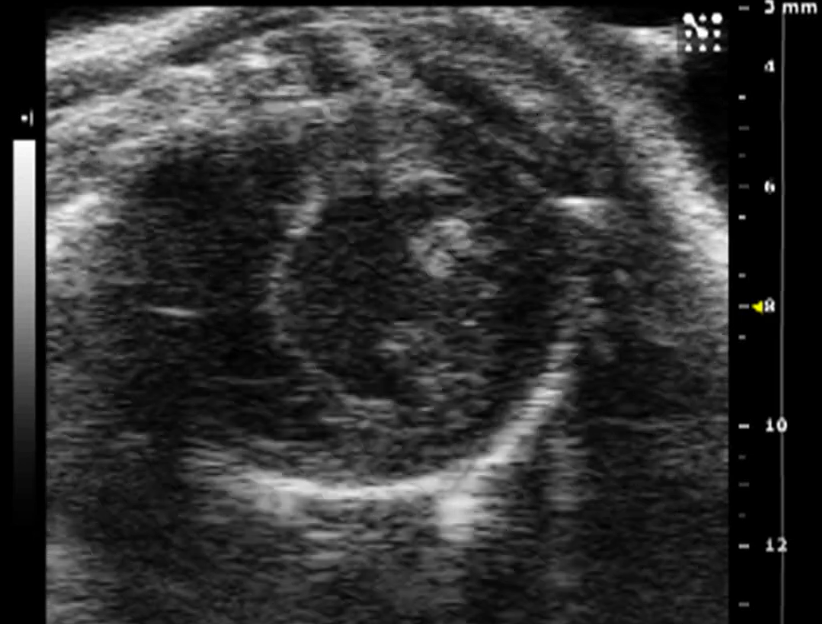

PCIC houses the ultrasound Vevo 2100 (Fujifilm Visualsonics Inc.). This unique technology allows acquiring real time images with high resolution for structural and functional imaging. It is perfect for assessing heart anatomy and function (echocardiography) in mice and rats. Transducers ranging from 13 to 55 MHz are available for imaging of vascular tumors (up to 14mm) to large tumors (<250g) along cardiovascular imaging. Multiple modes allow for additional analysis of blood flow and pressure.

Examples of ultrasound images (blood flow analysis) acquired by our Vevo 2100